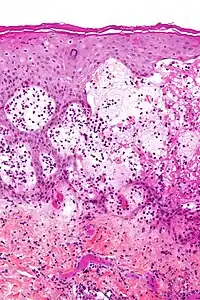

| Micrograph of gestational pemphigoid showing the characteristic subepidermal blisters and abundant eosinophils. HPS stain. | |